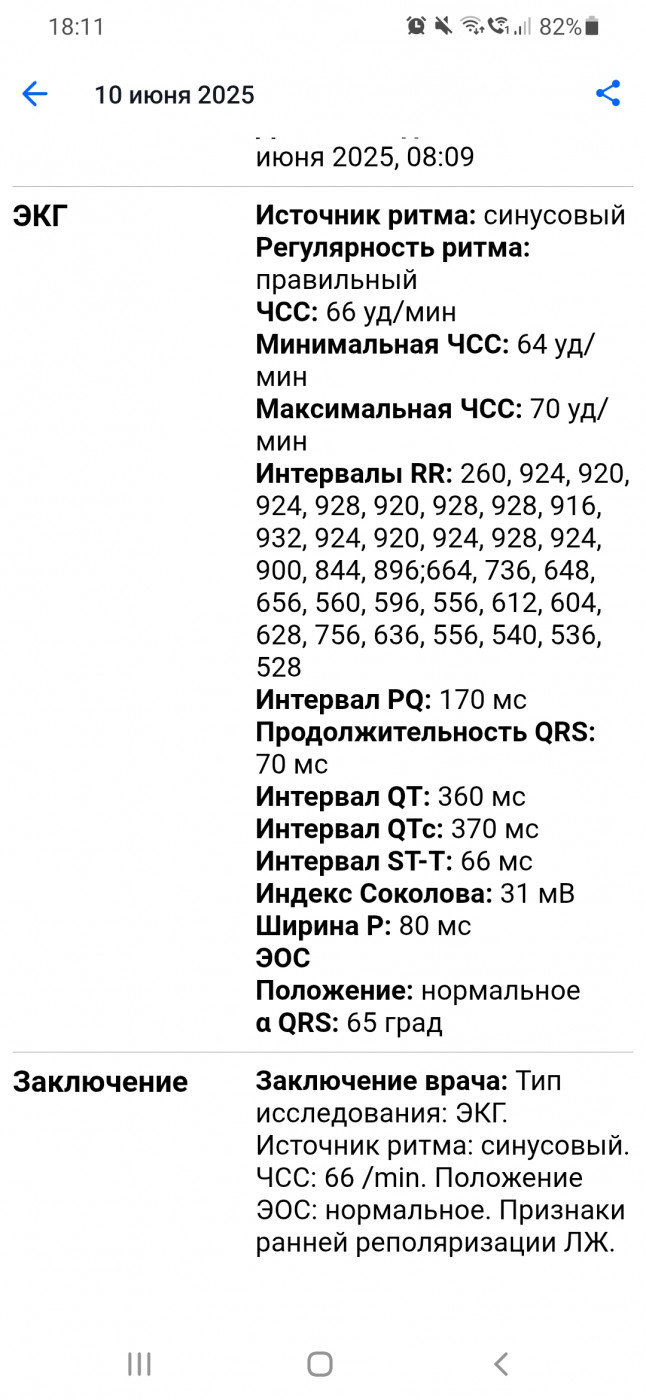

Экг: что означает результат исследования?

|

|

👍 +1 👎 |

Синдром ранней поляризации левого желудочка

|

|

👍 0 👎 |